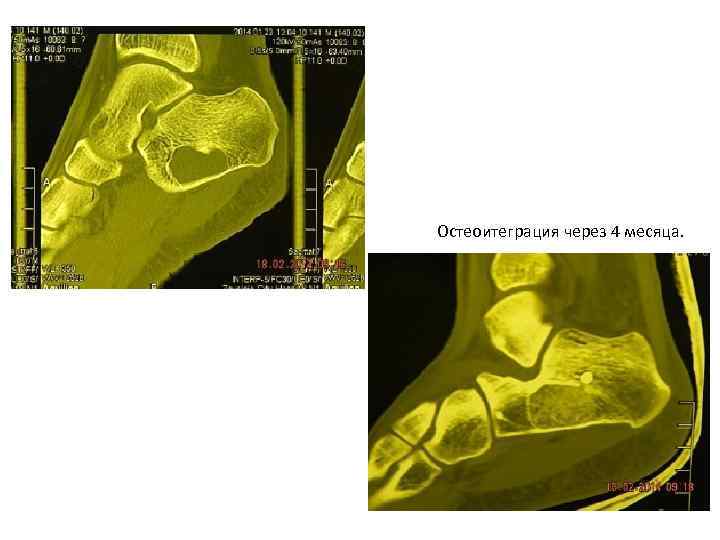

Остеоитеграция через 4 месяца.